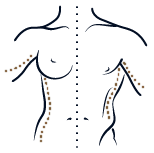

CIRUGÍA DE LA MAMA

Procedimiento quirúrgico para mejorar el tamaño y la forma del seno

CIRUGÍA DE LA MAMA

Intervención quirúrgica para disminuir el volumen y el peso del seno

CIRUGÍA DE LA MAMA

Cirugía para corregir las mamas tuberosas y darle un aspecto más natural

CIRUGÍA DE LA MAMA

Técnica que se ocupa de restaurar el pecho caído y darle un aspecto más juvenil

CIRUGÍA DE LA MAMA

Procedimiento quirúrgico para cambiar el tamaño y la forma del seno con prótesis

CIRUGÍA DE LA MAMA

Intervención quirúrgica para eliminar los senos y construir un pectoral

CIRUGÍA DE LA MAMA

Reconstrucción de la mama tras su extirpación debida a enfermedades u otros problemas

Lipoescultura Liposucción

CIRUGÍA CORPORAL

Modelado de la figura, mejorando, a nivel superficial, las zonas de flacidez residual.

Remodelación de la silueta con células de grasa del paciente para aportar volumen a otras zonas

Abdominoplastia

CIRUGÍA CORPORAL

Conseguir un abdomen más plano, más firme y una cintura más estrecha